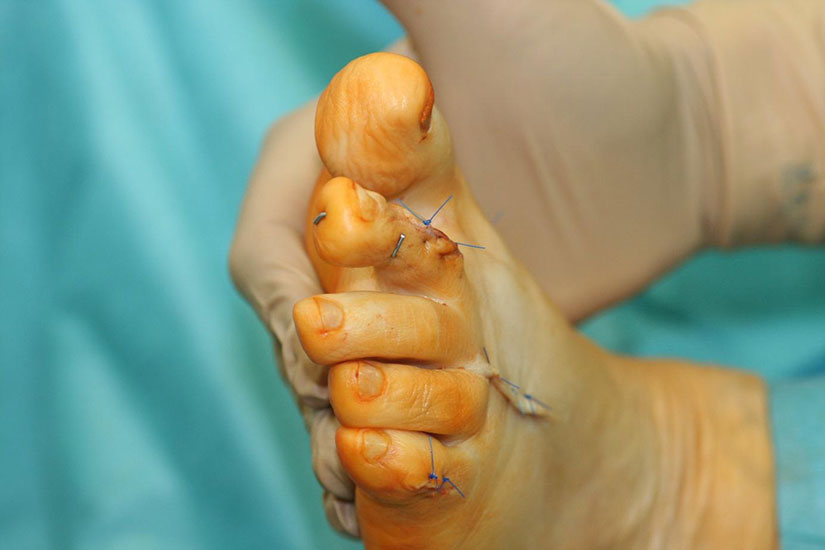

PIP-Arthrodese unter Verwendung des Pro-Toe®VO-intramedullären Implantates

Die vorbereitenden Operationsschritte werden im Abschnitt „PIP-Arthrodese mit K-Draht-Fixierung“ in den Abbildungen 1.1 bis 1.7 beschrieben.

• Direkt postoperativ muss auf eine ausreichende Durchblutung der korrigierten Zehe geachtet werden. Sollte die Zehe nach maximal 10 Minuten Anzeichen einer anhaltenden Durchblutungsstörung zeigen, wird zunächst das gesamte kompressive Verbandmaterial entfernt, Elevation vermieden bzw. der betroffene Fuß tiefer gelagert. Bei persistierender Durchblutungsstörung können lokale Erwärmung der Zehe sowie lokale Applikation einer Nitroglyzerinsalbe zu einer Vasodilatation führen. Der K-Draht kann bei anhaltender Durchblutungsstörung im ersten Schritt leicht im Bereich des PIP-Gelenkes gebogen werden. Beim Ausbleiben einer Verbesserung der Durchblutung muss dieser noch im Aufwachraum entfernt werden. Bei Verwendung eines intramedullären Implantats ist ggf. eine sofortige operative Revision mit Entspannung der  Weichteilstrukturen durchzuführen.